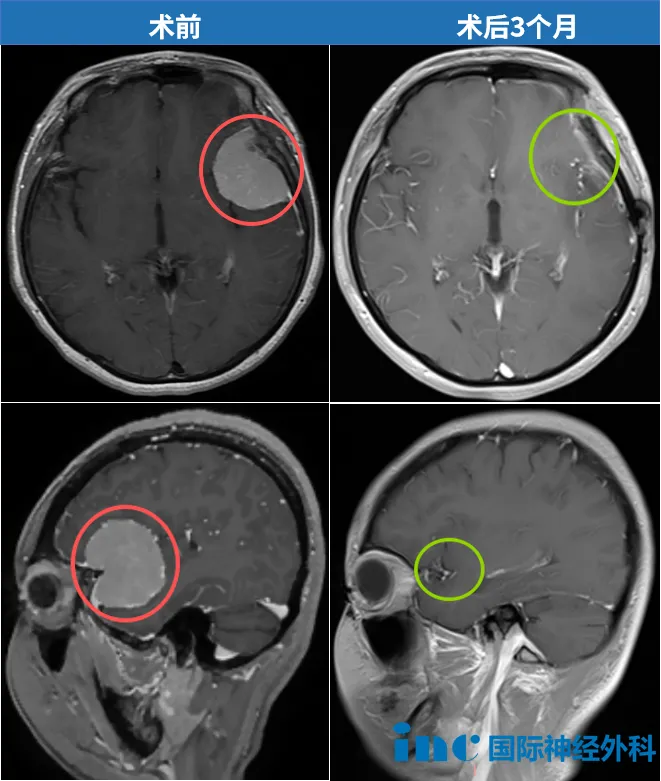

“病灶现在已经不存在了。影像上没有任何肿瘤残留,也没有复发,一切都如预期般良好,她现在不需要任何辅助治疗。”

开颅术后3个月,我收到了INC巴特朗菲教授的术后随访报告。最让我激动的是,教授还在报告上用中文写了四个字:“不能更好”。这一刻我知道,这场与脑膜瘤的抗争,我赢了。

“说话完全没问题,手脚活动也正常,精神状态比想象中好太多了!”当巴特朗菲教授亲自查房,确认肿瘤已完全切除时,我激动不已——我知道,自己做出了人生中正确的选择。